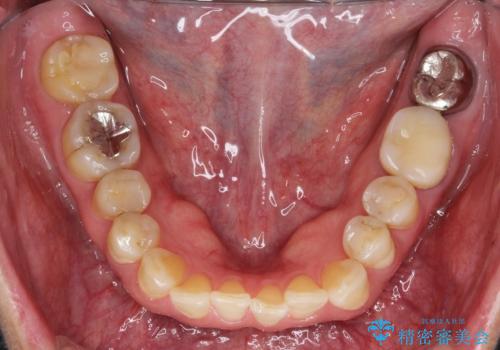

- 前歯のガタガタを主訴に来院されました。

上の歯の前突も気になってたため、奥歯の遠心移動も行いながらインビザラインにて治療を行いました。

今回は奥歯の遠心移動とIPRを行って配列しています。